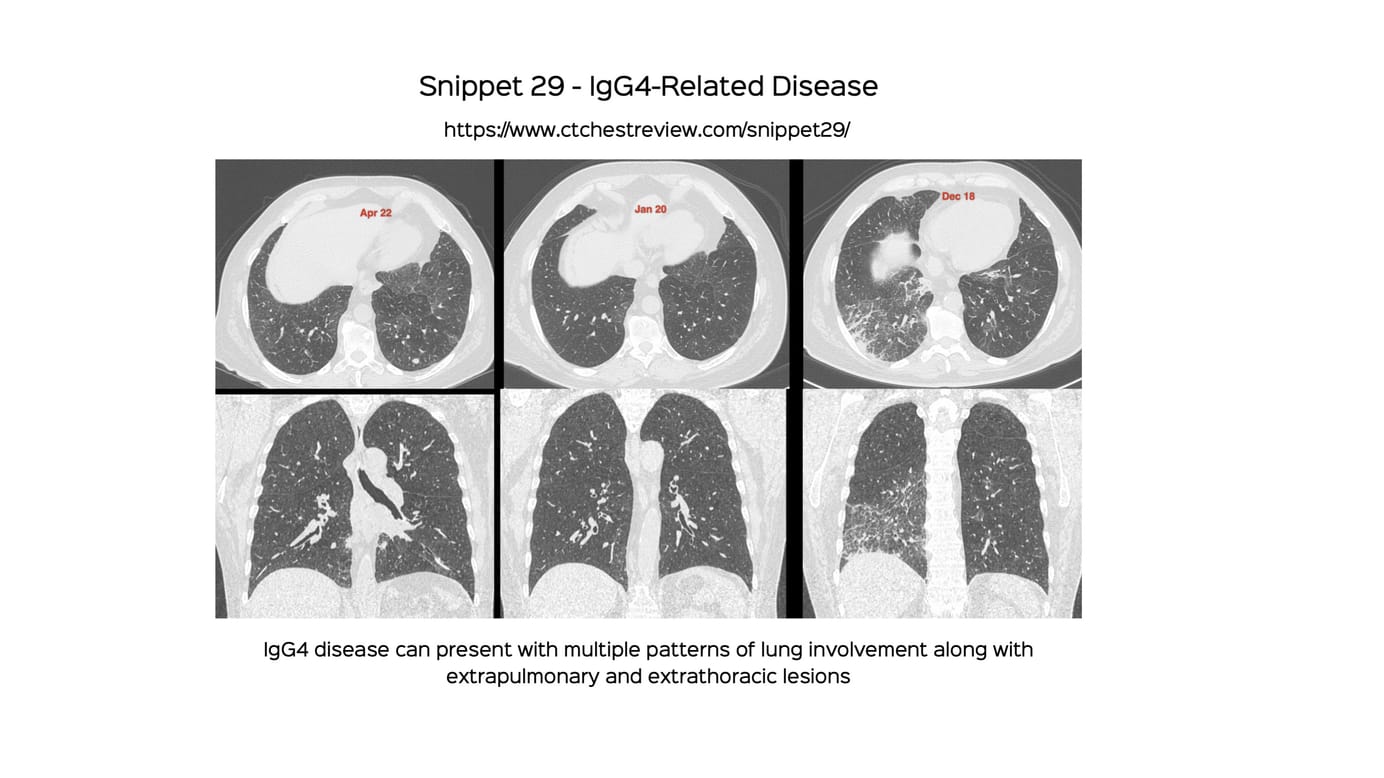

Snippet 29 - IgG4-Related Disease

A discussion of the various manifestations of IgG4-related disease - pulmonary, extrapulmonary and extrathoracic.

IgG4-related disease is an autoimmune process with infiltration of IgG4-plasma cells into tissues. It typically presents as a multi-organ, multicompartmental disease process.

The lung findings are myriad but often non-specific and it is not easy to make a prospective diagnosis, unless there are other organs like the lacrimal glands, salivary glands, pancreas, kidneys, aorta, etc involved.

This video goes through multi-system IgG4-related disease in general and then specifically looks at pulmonary and extra-pulmonary manifestations.